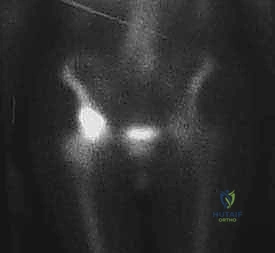

4. Bone Scan (Technetium Tc 99m): A whole-body bone scan is essential to rule out concomitant metastatic lesions, particularly in the ipsilateral femur. This helps us ensure we're not missing other sites that might compromise our surgical plan or patient prognosis. Our patient's scan showed no uptake in the ipsilateral femur or medial acetabular wall, which is excellent.

FIG 2 • B. Technetium Tc 99m bone scan showing uptake in the supra-acetabular region. No uptake is seen in the ipsilateral femur or medial acetabular wall.